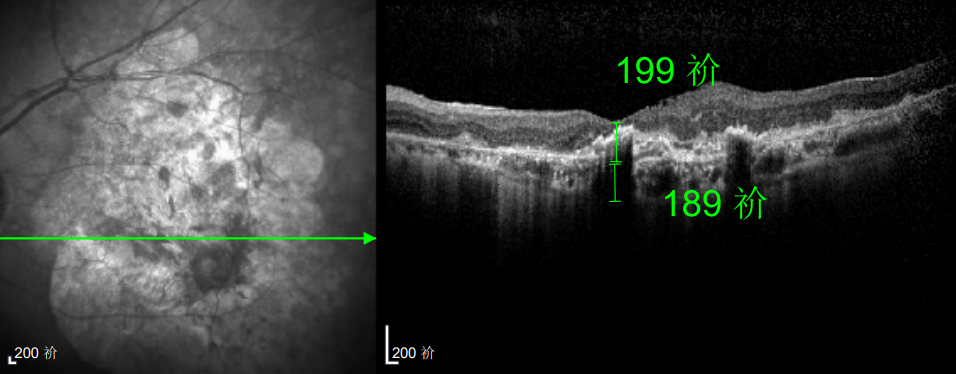

△延誤復查后的左眼